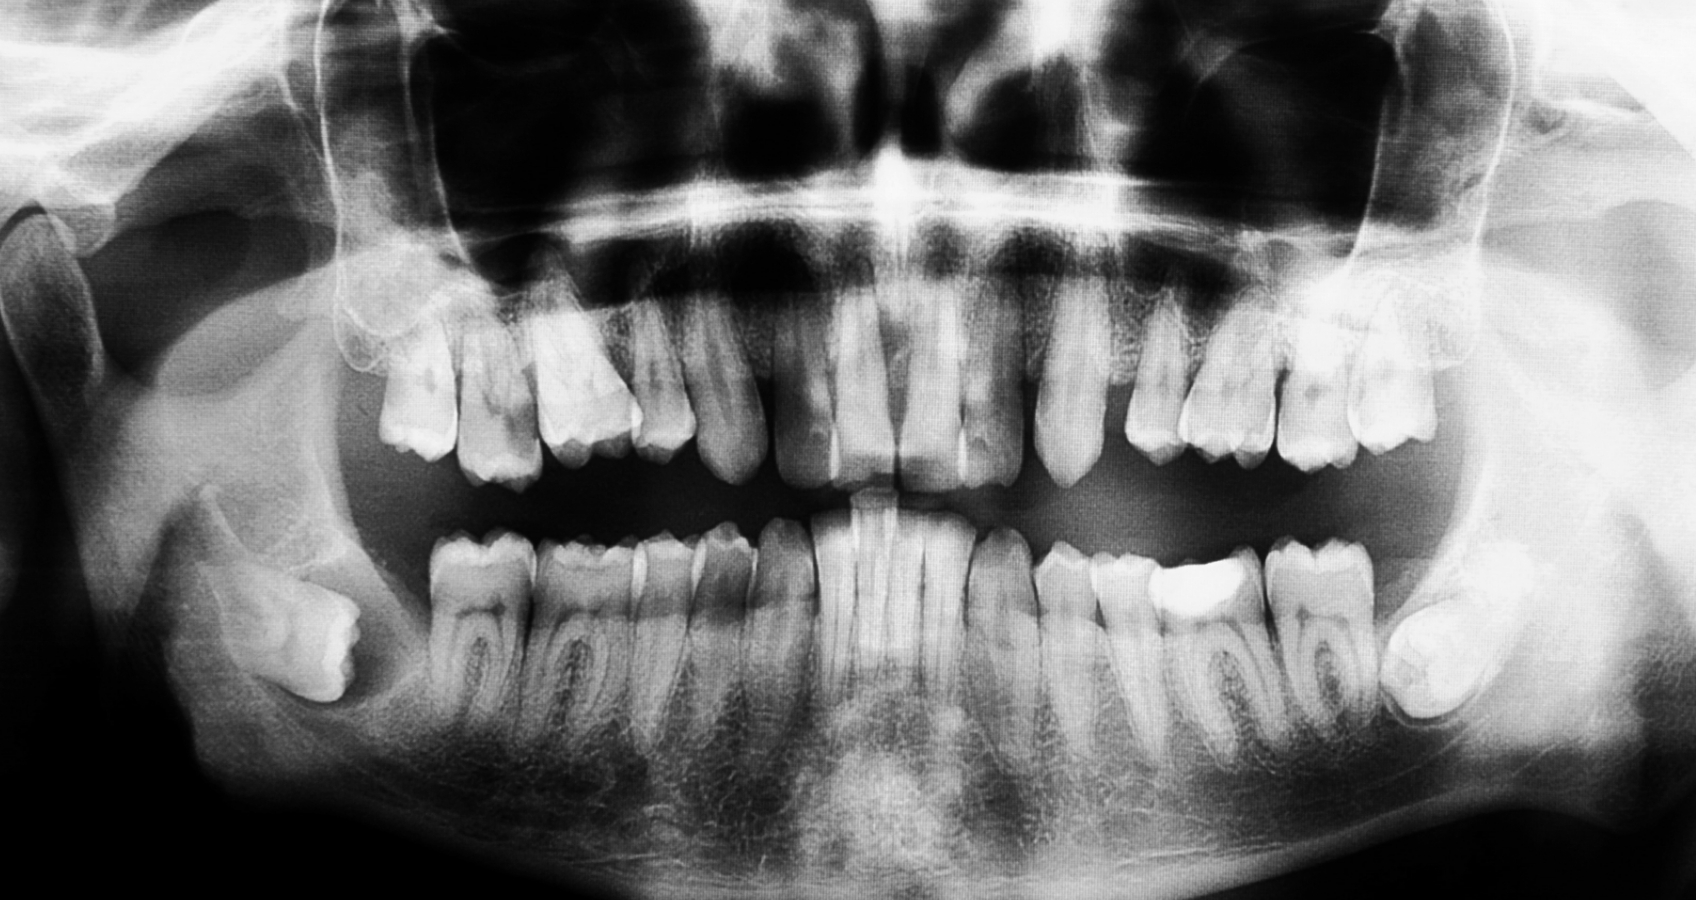

Dokładna diagnostyka – wykonujemy zdjęcie RTG lub tomografię 3D, aby zaplanować każdy etap zabiegu.

Chirurgiczne usunięcie zęba – w przypadku ósemek najczęściej stosujemy techniki segmentacji, czyli podziału zęba na mniejsze części. To standardowa procedura, która pozwala bezpiecznie usunąć ząb bez uszkodzenia otaczającej kości.